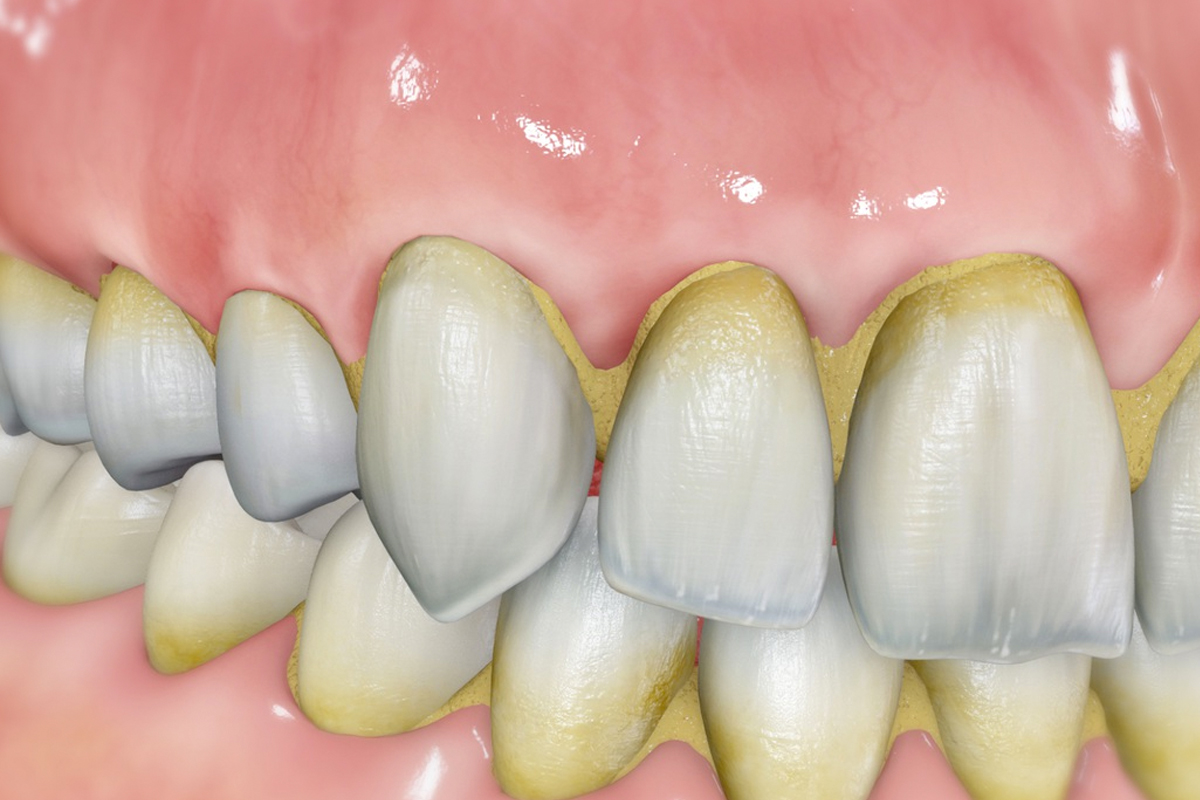

Los síntomas de la enfermedad periodontal son muy fáciles de detectar, como que las encías estén enrojecidas, inflamadas o que sangren al cepillarnos. También, puede darse el caso de que suframos de mal aliento o de que tengamos un sabor desagradable en la boca que no desaparece ni con el cepillado.

Las enfermedades de las encías tienen su origen en una mala higiene bucal, por lo que una correcta labor de prevención evitará una de las patologías de la boca más molestas.

la Periodontitis va más allá de la inflamación de las encías y se refiere también a la pérdida de hueso de soporte de los dientes, lo que, en futuro, sin el tratamiento adecuado, puede llevar a la pérdida dentaria en un futuro.

Una mala higiene bucodental provoca que se acumule sarro en los dientes, el cual ya no desaparece con el cepillado cotidiano de casa. Una limpieza profunda en la clínica dental puede ser la solución a este problema.